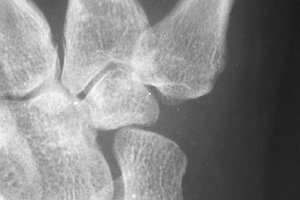

Another thumb, similar changes.